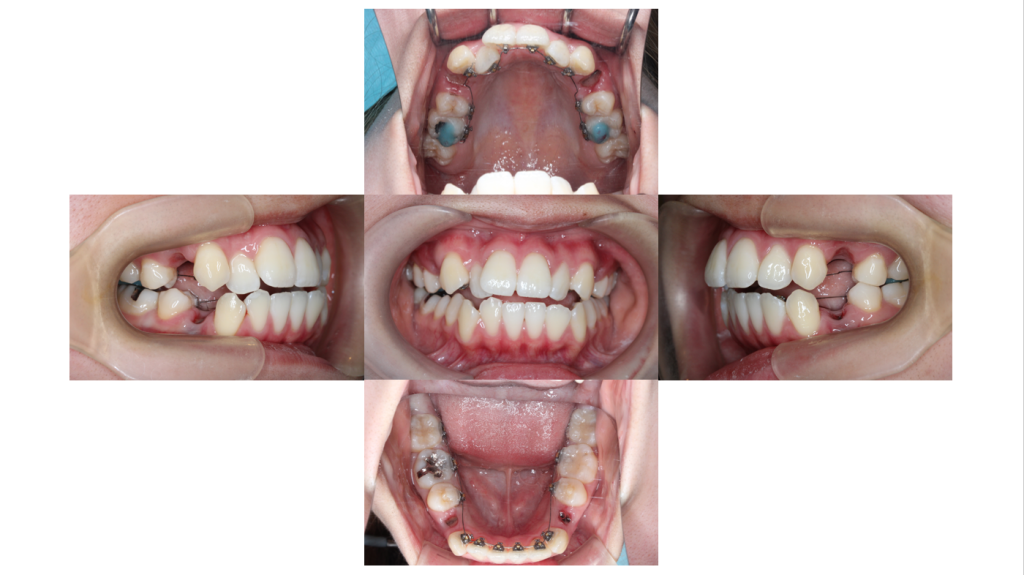

約2ヵ月経過

叢生・裏側矯正の症例内側に入り込んでいた右上の前歯が出てきました。